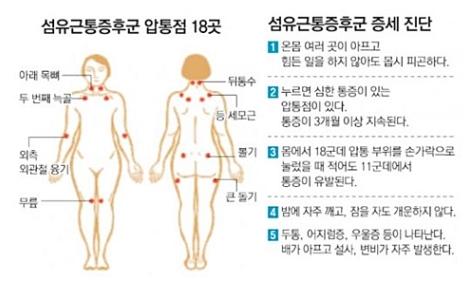

25세 대학생이고 골프선수인데 목이 너무 아파서 찿아온손님인데 온몸이 아프고 자고 나도 피로가 풀리지않고

몸이 여기 저기 만지는 곳마다 아프다고 한다 . 병원에서 특별한 진단도 나오지 않고 기운이 없고

특별한 이상이 없는데고 날씨가 흐릴려고 하면 더욱 심해진다고 한다

전형적인 태음인으로 겉으론 건강해 보이나 무리한 연습으로 체력이 많이 떨어져있고 시합을로 인한 심한 스트레스로

정신적인 것까지 겹처서 심신이 모두 지쳐있는것같다.손발이 얼음짝처럼 차갑고 배에 까스도 많이 차고 입안이늘 건조하고 ....